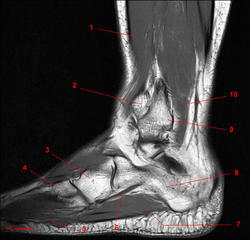

Рис. 16

1, Длинный разгибатель пальцев. 2, Малоберцовая кость. 3, Сухожилие длинной малоберцовой мышцы. 4, Сухожилие короткай малоберцовой мышцы. 5, Пятая плюсневая кость. 6, Мышца, отводящая мизинец стопы. 7, Длинная малоберцовая мышца.